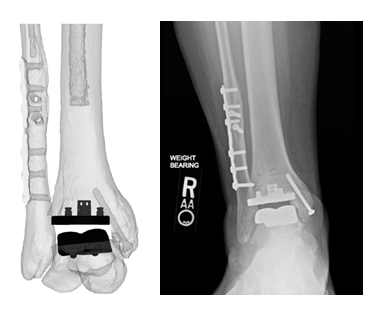

Dr. Oliver Schipper and Dr. Constantine Demetracopoulos, two of the pilot launch surgeons that are utilizing the technology, have each completed multiple cases utilizing the Vantage Ankle PSI to date. The Vantage Ankle PSI solution allowed Dr. Schipper to address a challenging case with pre-existing hardware requiring deformity correction with good agreement between surgical plan and clinical outcome, as evidenced by the images below.

Dr. Schipper’s PSIs and final patient x-rays